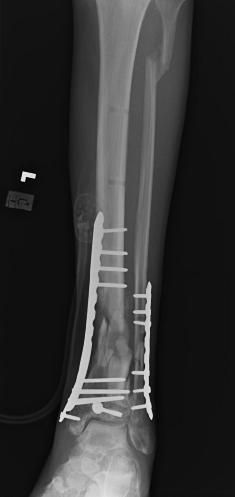

Post-corrective surgery X-Rays of the damaged right & left legs / ankles

The first two x-rays show Liam’s left ankle and pelvis prior to the accident. For comparison purposes it is interesting to see the

differences. The next x-rays were taken after the corrective surgery performed by Dr. Armendariz. Noticed that Dr. Armendariz has used tibia

bracing and also aligned the bone fragments of the left leg so that they could heal in the proper orientation. The external fixation has been

removed and Liam’s left foot has been returned to a more natural alignment.